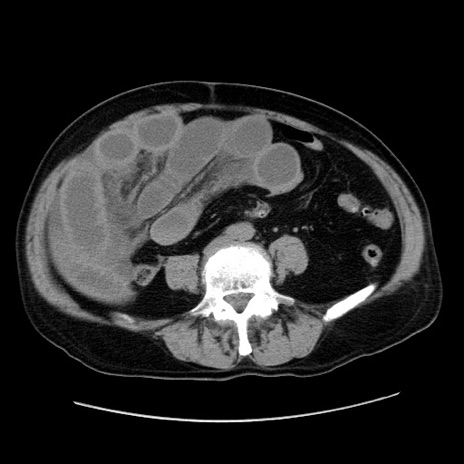

症例30(横断像)

【症例】80歳代男性

【主訴】臍周囲痛

【現病歴】約6時間前から臍下部痛が出現。次第に腹部膨隆・背部痛も生じてきたため来院。背部痛の場所は変化しない。

【身体所見】意識清明、BT 36.3℃、BP  131/87mmHg、P 87bpm、SpO2 100%(RA)、臍周囲自発痛・圧痛あり、反跳痛なし、自発痛部位に一致して板状硬あり、腹部膨隆、腸雑音減弱、CVA tenderness両側陰性。

【データ】WBC 19600、CRP 0.33